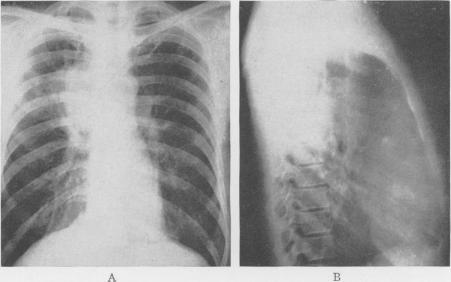

Bronchiogenic Cysts of the Mediastinum.